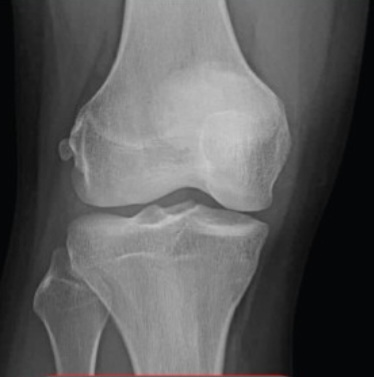

현재키는 169~170cm입니다 몸무게는 73kg~74kg정도 됩니다 밑에 사진을 보고 성인이 됬을때 최종키가 얼마나 됬을지 알려주세요 그리고 골 연령 나이도 알려주시면 감사하겠습니다 부모님키:아버지:170cm 어머니:160cm 입니다